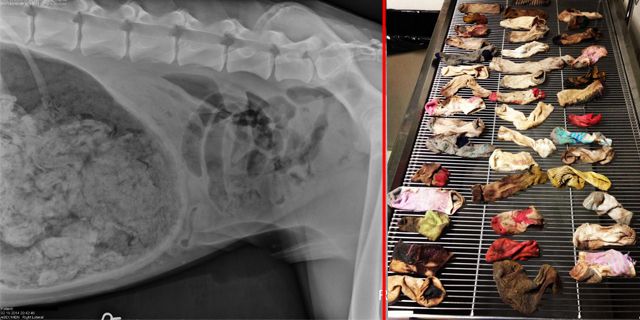

Bild: DoveLewis Emergency Animal Hospital